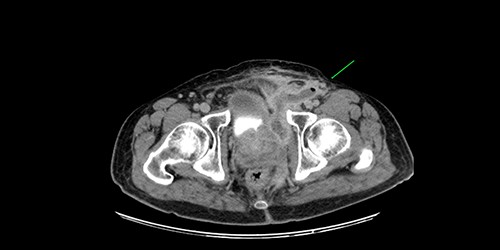

A 61-year-old diabetic patient was admitted from emergency department with septic signs; fever of 39°C, white blood cell count of 20.000/μl, C-reactive protein levels of 156 mg/l and blood glucose levels of 280 mg/dl. For the past 10 days, the patient has noted malodorous anorectal pus discharge, as well as anorectal and suprapubic pain. During macroscopic examination of the perineum, a left-sided abscess in the ischiorectal fossa was identified, with an opening lateral to the sphincteric anal system draining pus. Subsequent digital rectal examination of the anorectal canal could not be completed due to pain, but the initial effort revealed large amounts of pus discharged from anorectal canal. CT and MRI demonstrated an abscess situated in the left ischiorectal fossa and a large supralevator abscess extending cephalad in the extraperitoneal space with a long fistulous tract containing liquid (pus) and gas bubbles, up to the suprapubic area, where erythema with an undulating pus collection below the skin was noted; laterally the pus collection extended up to the left ilio-femoral vessel canal. CT (Fig. 1) and MRI (Fig. 2) were conclusive for the above entity, aptly demonstrating the presence of the two abscess cavities. Proctoscopy under general anesthesia revealed a protruding extra-rectal mass in the left lateral and inferior segment of the rectal ampulla. Finger pressure at this point was accompanied with pus exit from the posterior dentate line of the anal canal at 6 o’clock, through an opening of 1–2 mm in size. Surgery was addressed in three main locations of the pus collection with goal to drain completely the pus; the abscess of the left ischiorectal fossa was drained with enlargement of the external opening of fistula; after curettage, debridement and washing of abscess cavity, a probe was used to detect the internal opening exactly at the posterior dentate line at 6 o’clock. The fistula was characterized as full trans-sphincteric with an extra-sphincteric component in the ischiorectal fossa leading up to the skin. A non-cutting vessel loop drainage seton was then placed. The supralevator abscess was then easily drained from the opening in the posterior dentate line by finger pressure in the left rectal ampulla. A probe following the route of the internal opening upwards to supralevator space led to pus evacuation, allowing this space to be thoroughly washed with water saline solution, using a syringe with a vein catheter. Finally, the suprapubic area was drained with a small stab incision, followed by washing with normal saline. There was a prompt recovery postoperatively, tight control of blood glucose levels, whereas a CT performed 7 days postoperatively (Fig. 3), demonstrated an empty supralevator space with a fistulous tract still present, albeit with significant regression of inflammatory changes.

CT of the lower pelvis; supralevator abscess, with extension upward in touch with the left ilio-femoral vessels. The abscess cavity is shown approaching the skin with a long fistulous tract containing liquid (pus) and gas bubbles (green arrow).